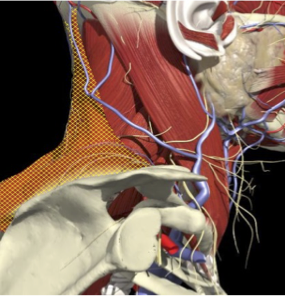

ROLE OF EMG

-

Accuracy of Muscle Localization

Planning of muscles to inject - determination of active muscles

Localization of endplates

- Less problems with diffusion

- Muscles deep

- Not easily identified by surface landmarks

- Not palpable on examination

ACCURACY OF LOCALIZATION – DEEPER LAYERS

INJECTION SITES